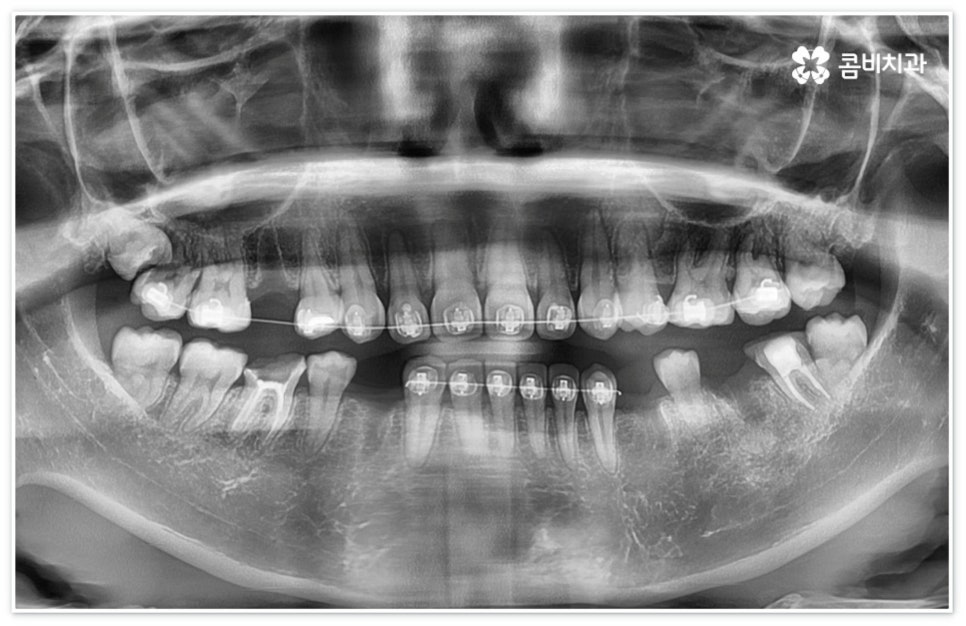

이때 환자분들마다 상황이 다를 수 있는데 예를 들어 교정 치료 중 충치 치료 (신경 치료) 및 발치와 임플란트 식립과 같은 고난도의 치료들을 함께 진행해야 하는 복잡한 케이스의 경우에는 더욱 시술자의 숙련도가 중요하다고 할 수 있어요. 의료진의 자격증, 경력 사항, 분과별 협진 여부 등을 잘 알아 보시고 필요한 치료들을 모두 통합적으로 진행할 수 있는지, 또한 환자분들의 상황을 꼼꼼하게 살필 수 있는 3D CT 와 같은 정밀 검진 기계를 갖추고 있는지 등을 체크해 보신 후에 처음부터 끝까지 책임 진료하는 의료진과 철저한 케어 시스템을 갖추고 있는 치과를 선택하셔서 제 때 필요한 치료를 받으시길 권유드리고 있습니다.